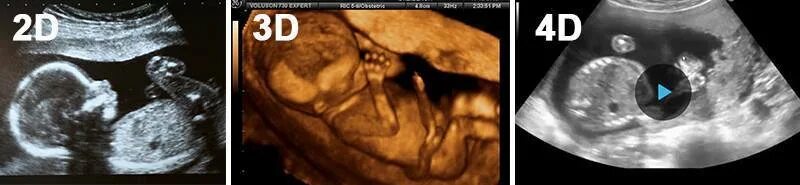

Второй скрининг 21 неделе